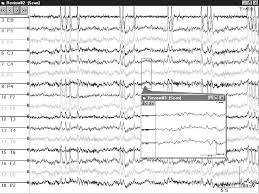

L'elettroencefalogramma è la registrazione dell'attività bioelettrica cerebrale ottenuta posizionando dei sensori (elettrodi di superficie) sulla testa.

Indosserete una cuffia elastica, su cui sono predisposti gli elettrodi che, appoggiati al cuoio capelluto, registrano l'attività elettrica cerebrale,

II tecnico applicherà all'interno degli elettrodi un GEL elettroconduttore (inodore, incolore, anallergico) che consente il contatto elettrodi – cuoio capelluto.

L'esame dura circa 20 minuti. Si svolge quasi per intero ad occhi chiusi.

Durante i primi 10 minuti vi chiederemo di aprire e chiudere gli occhi più volte.

Durante i restanti 10 minuti vi faremo eseguire due semplici e non dolorose manovre: una respirazione profonda prolungata ed una stimolazione luminosa intermittente.